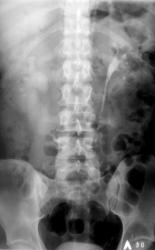

Иллюстрации 10, 11. 30 минута. Справа определяется эктазированная полая система (прегидронефротическая трансформация).

Вывод: Мочекаменная болезнь с локализацией конкрементов в полой системе левой почки и в нижней трети правого мочеточника. Эктазия полой системы правой почки.